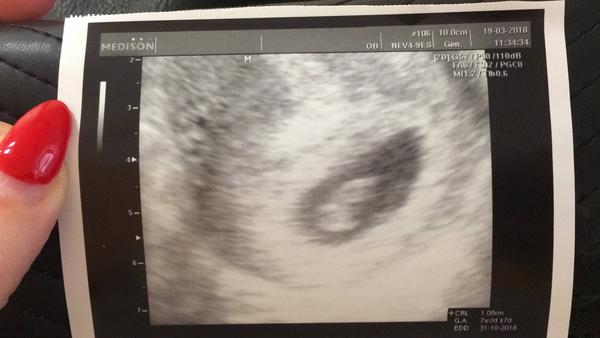

@girafkag dobre 🙂 je na spravnem miste a uz bylo i srdicko 🙂 a jak se ti dari?je to uz lepsi?napada me,nevis jak se po ET pocita stari tehotenstvi?prekvapilo me,ze se pri kontrole ptal na termin transferu a ne posledni ms...

@miracleelcarim a jeste jedna otazka,dostala si fotku z ultrazvuku 🙂 je mi jasne,ze do ramecku se jeste nehodi,ale stejne se na ni moc tesim